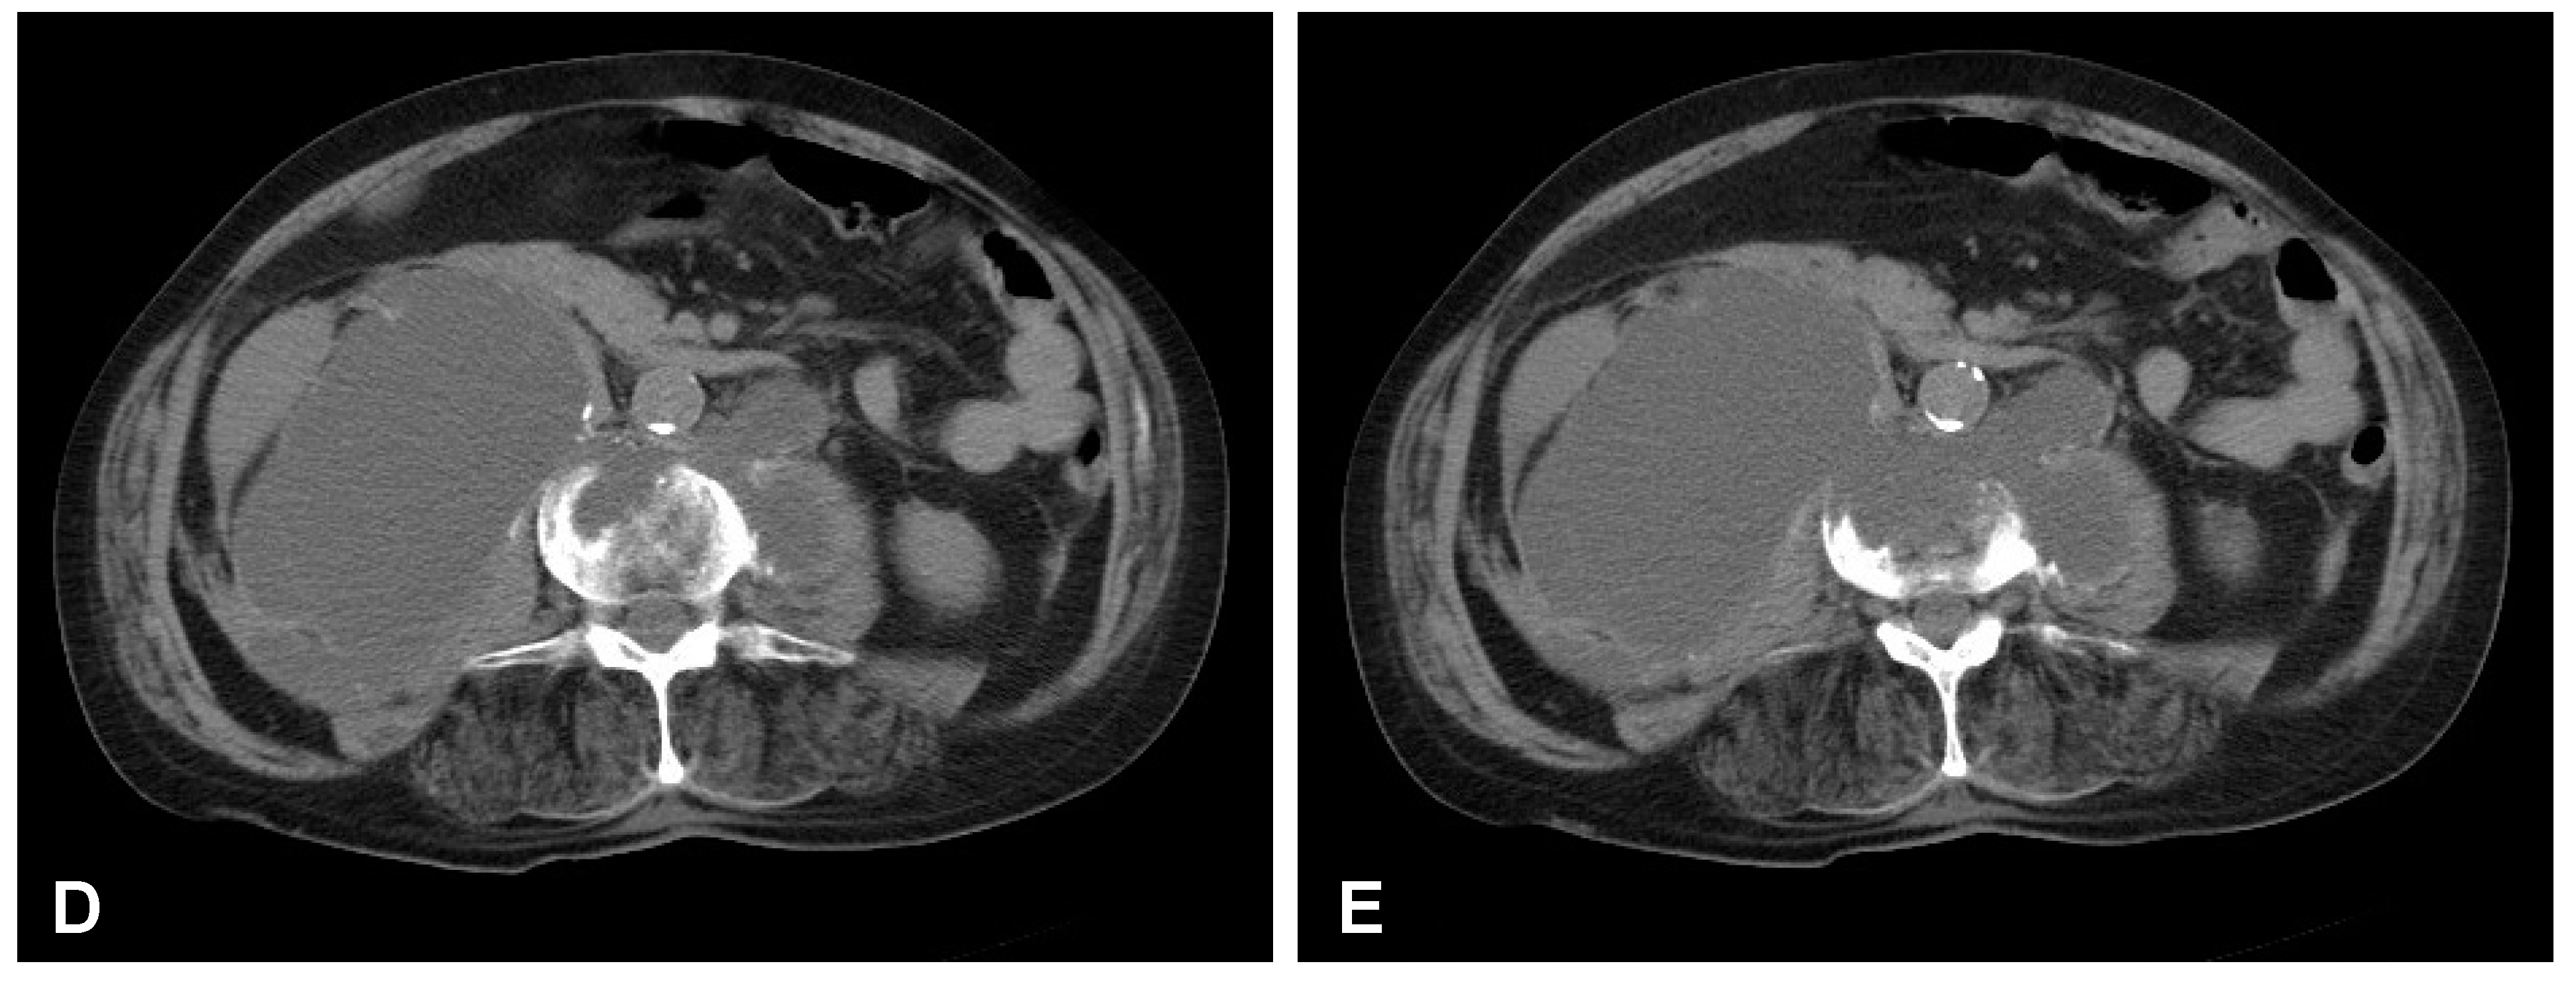

Figure 7. Postoperative axial CT scans (contrast enhanced delayed phase) demonstrating evidence of post-traumatic right ureteral injury, urine leakage, and hydronephroureter (AF).

After initial diagnostics and preparations, the patient was transferred to the operating room. The posterior percutaneous transpedicular stabilization at the L2-L3-L5-S1 levels (Mantis; Stryker, Kalamazoo, MI, USA) with cement augmentation (VertaPlex HV; Stryker, Kalamazoo, MI, USA) for each inserted screw (4 mm × 6.5 mm/50 mm; 4 mm × 6.5 mm/45 mm) under intraoperative 2-dimensional (2-D) fluoroscopy control was performed in the first stage of surgery. In the second stage of surgery, from a lateral approach, the left side of the retroperitoneal cyst was emptied, and watery/light yellow fluid similar to urine was obtained. Therefore, a distractible vertebral body replacement implant (AsterX; Medtronic, Minneapolis, MN, USA) was placed between the L3 and L4 bodies with the placement of a retroperitoneal precutaneus Redon drainage system. A control CT scan performed one day after the operation revealed the correct placement of all the implants (Figure 5 and Figure 6). The second CE-CT scan performed two days after surgery consecutively showed evidence of post-traumatic right ureteral injury, urine leakage, and hydronephroureter (Figure 7). The general examination of intraoperatively obtained fluid revealed the following results: pH: 9.0; protein: 600 mg/dL; transparency and color before centrifugation: sanguine and cloudy; transparency and color before centrifugation: transparent and dark yellow; absolute leukocytes (LEU): 1197 cells/μL; and sediment: single round epithelium in the sample with erythrocytes loosely cover the field of vision (15–20 in the counterfield). The microbial culture of the intraoperative obtained fluid after 7 days was negative. After 4 days, the patient was transferred to another local hospital specializing in urological care. Due to the overall late presentation covering advanced hydronephrosis, ureteric stricture formation, and non-functional kidney, the nephrectomy and ureter ligation were performed. After urological treatment, the patient has been on follow-up for 2 years with no evidence of neurological or urological problems.